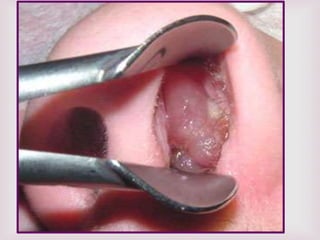

TRATAMIENTO QUIRÚRGICO

Polipectomía endoscópica.

Indicaciones:

1.- pacientes con obstrucción nasal grave.

2.- individuos con rinosinusitis recurrente debido a

los pólipos por obstrucción del drenaje.

3.- personas con mala respuesta al tratamiento

médico.

4.- individuos con contraindicación para el uso de

esteroides.

El tratamiento quirúrgico esta indicado cuando no hay respuesta al

tratamiento medico.

 Pólipos nasales sin patología de senos paranasales = POLIPECTOMIA DE

ASA.

 Pólipos nasales con sinusitis maxilar = CALDWELL LUC.

 Pólipos nasales con sinusitis etmoidal = ETMOIDECTOMIA.

 Pólipos nasales con sinusitis esfenoidal = ESFENOIDECTOMIA.

 La cirugía endoscópica esta indicada en poliposis nasal masiva y

recidivas.

POLIPECTOMIA DE ASA.